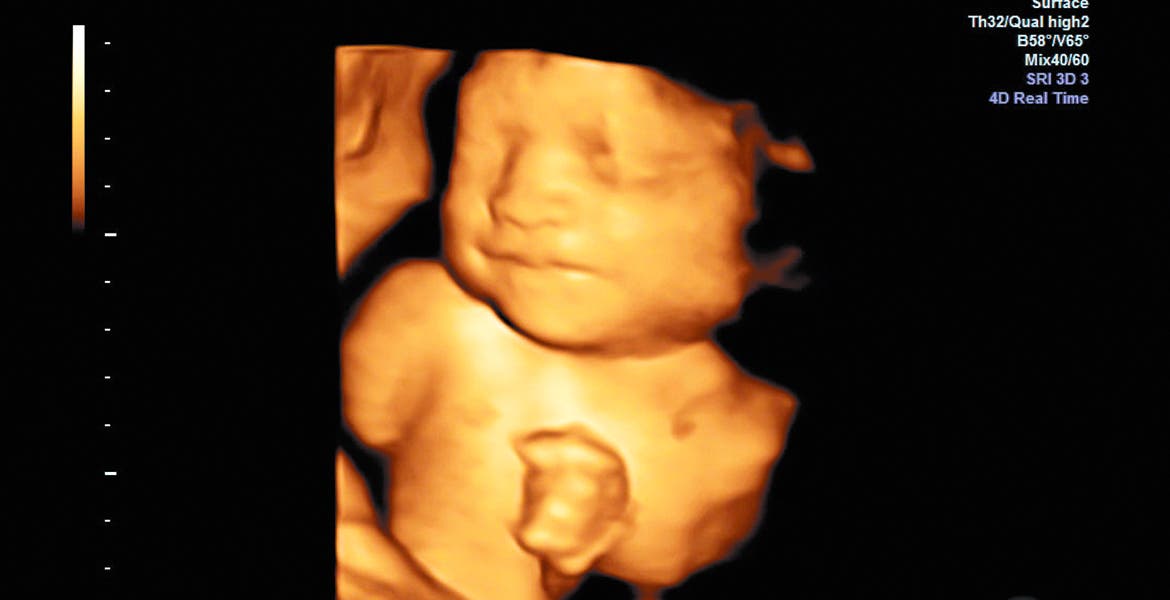

A detalle. El investigador busca que mediante software el ultrasonido detecte posibles riesgos de parto prematuro.